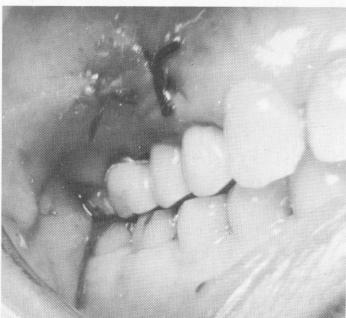

Fig. 15-68. Three weeks later, the tissue looks excellent.

4 Excellent tissue healing after endosseous pin implantation in maxilla